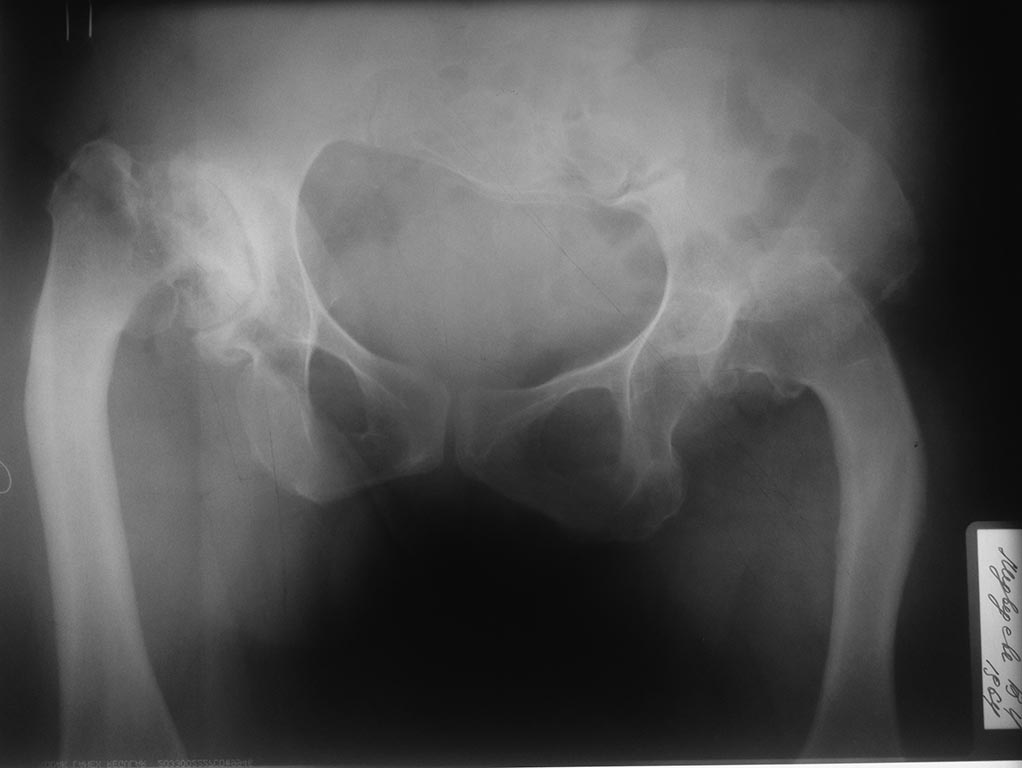

Пациентка 48 лет, врожденная аномалия скелета. В настоящее время

поступила с диагнозом:Диспластический коксартроз III ст справа, вывих

левого бедра (Crowe IV)/Гонартроз слева III. Варусные деформации обоих

бедер. Сгибательная, приводящая, ротационная контрактура правого

тазобедренного сустава. Сгибательная контрактура левого коленного